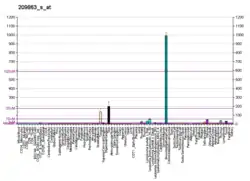

TP63 has been observed overexpressed in Vulvar Squamous Cell Carcinoma samples, in association with hypermethylation-Induced inactivation of the IRF6 tumor suppressor gene. [22] Indeed, mRNA levels of TP63 tested higher in Vulvar cancer samples when compared with those of normal skin and preneoplastic vulvar lesions, thus underscoring an epigenetic cross-link between IRF6 gene and the oncogene TP63. [22]

There is some evidence that the expression of p63 is regulated by the microRNA miR-203[28][29] and USP28 at protein level [30][31]